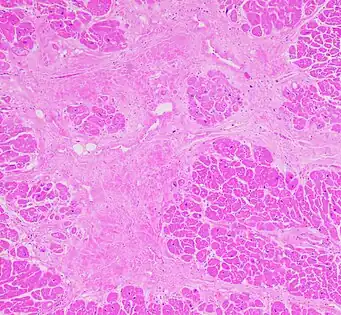

Micrograph of healthy myocardium versus interstitial fibrosis in dilated cardiomyopathy. Alcian blue stain. The fibrosis is either evenly distributed between myocytes or follows anatomic structures such as blood vessels. Interstitial fibrosis of chronic ischemic heart disease, H&E stain, with associated relatively well organized myocardial bundles

Interstitial fibrosis of chronic ischemic heart disease, H&E stain, with associated relatively well organized myocardial bundles Subepicardial fibrosis (epicardium at top).